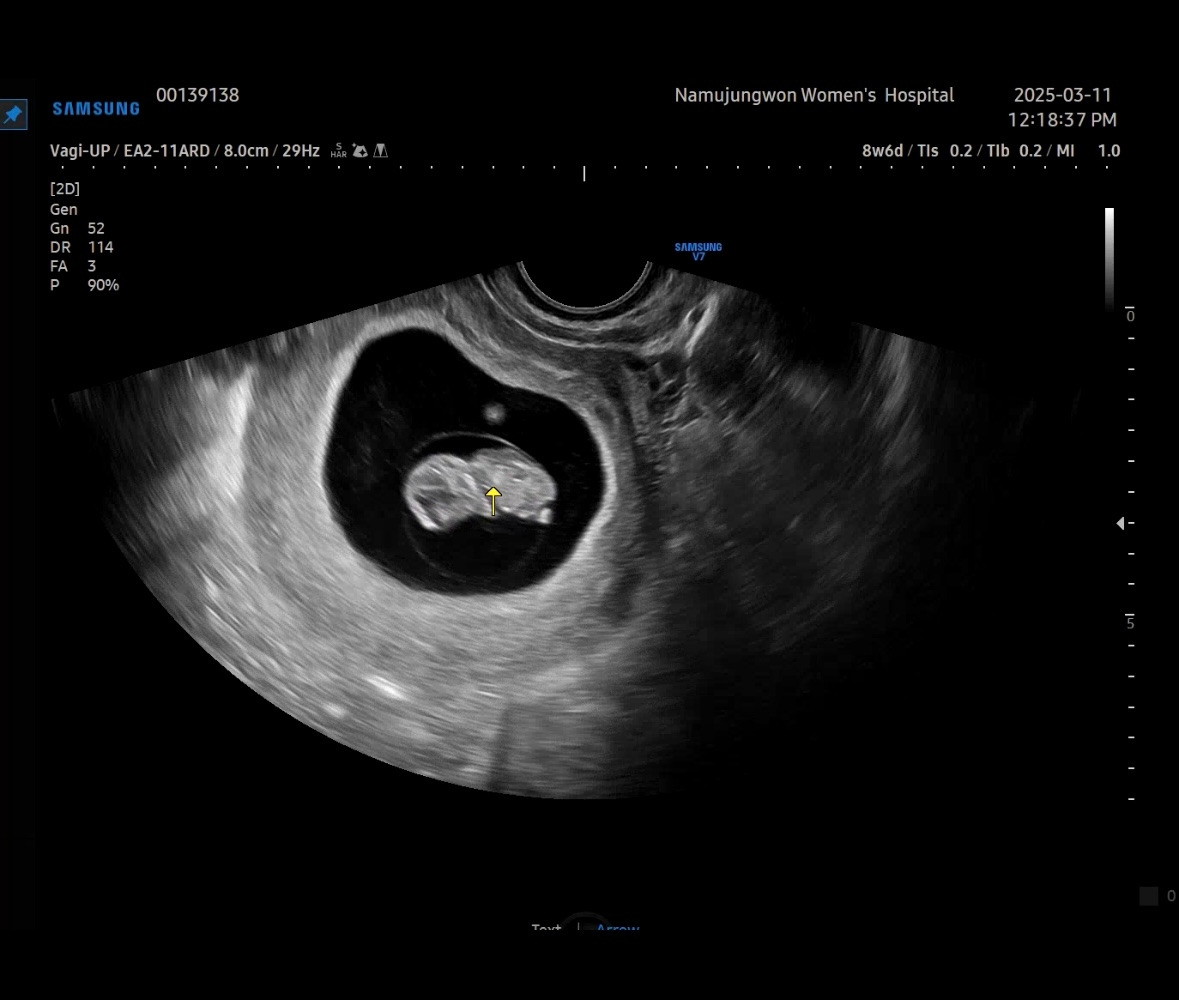

처음 알게 된 게 4주 차, 그 주 토요일 바로 산부인과를 가서 만난 작고 동그란 난황. 5주 차 3일째였다.

난황은 수정 후, 약 2주 무렵 생기며, 초기 영양 공급 등 임신 초기 발달에 중요한 역할을 한다. 태반이 생기기 전까지 태아에게 영양을 주고, 시간이 지나면서 역할을 마치고 점점 작아지거나 사라진다.

난황이 아기가 되는 건 아니고 난황 옆에 아주 작은 점처럼 아기가 있다고 하는 데, 이 시기에는 거의 보이지 않기 때문에 아기가 아니라고ㅎㅎ 병원을 나오고 의사 선생님이 아직 아기가 아니에요라고 한 말이 되게 강하게 머리에 남았었다.